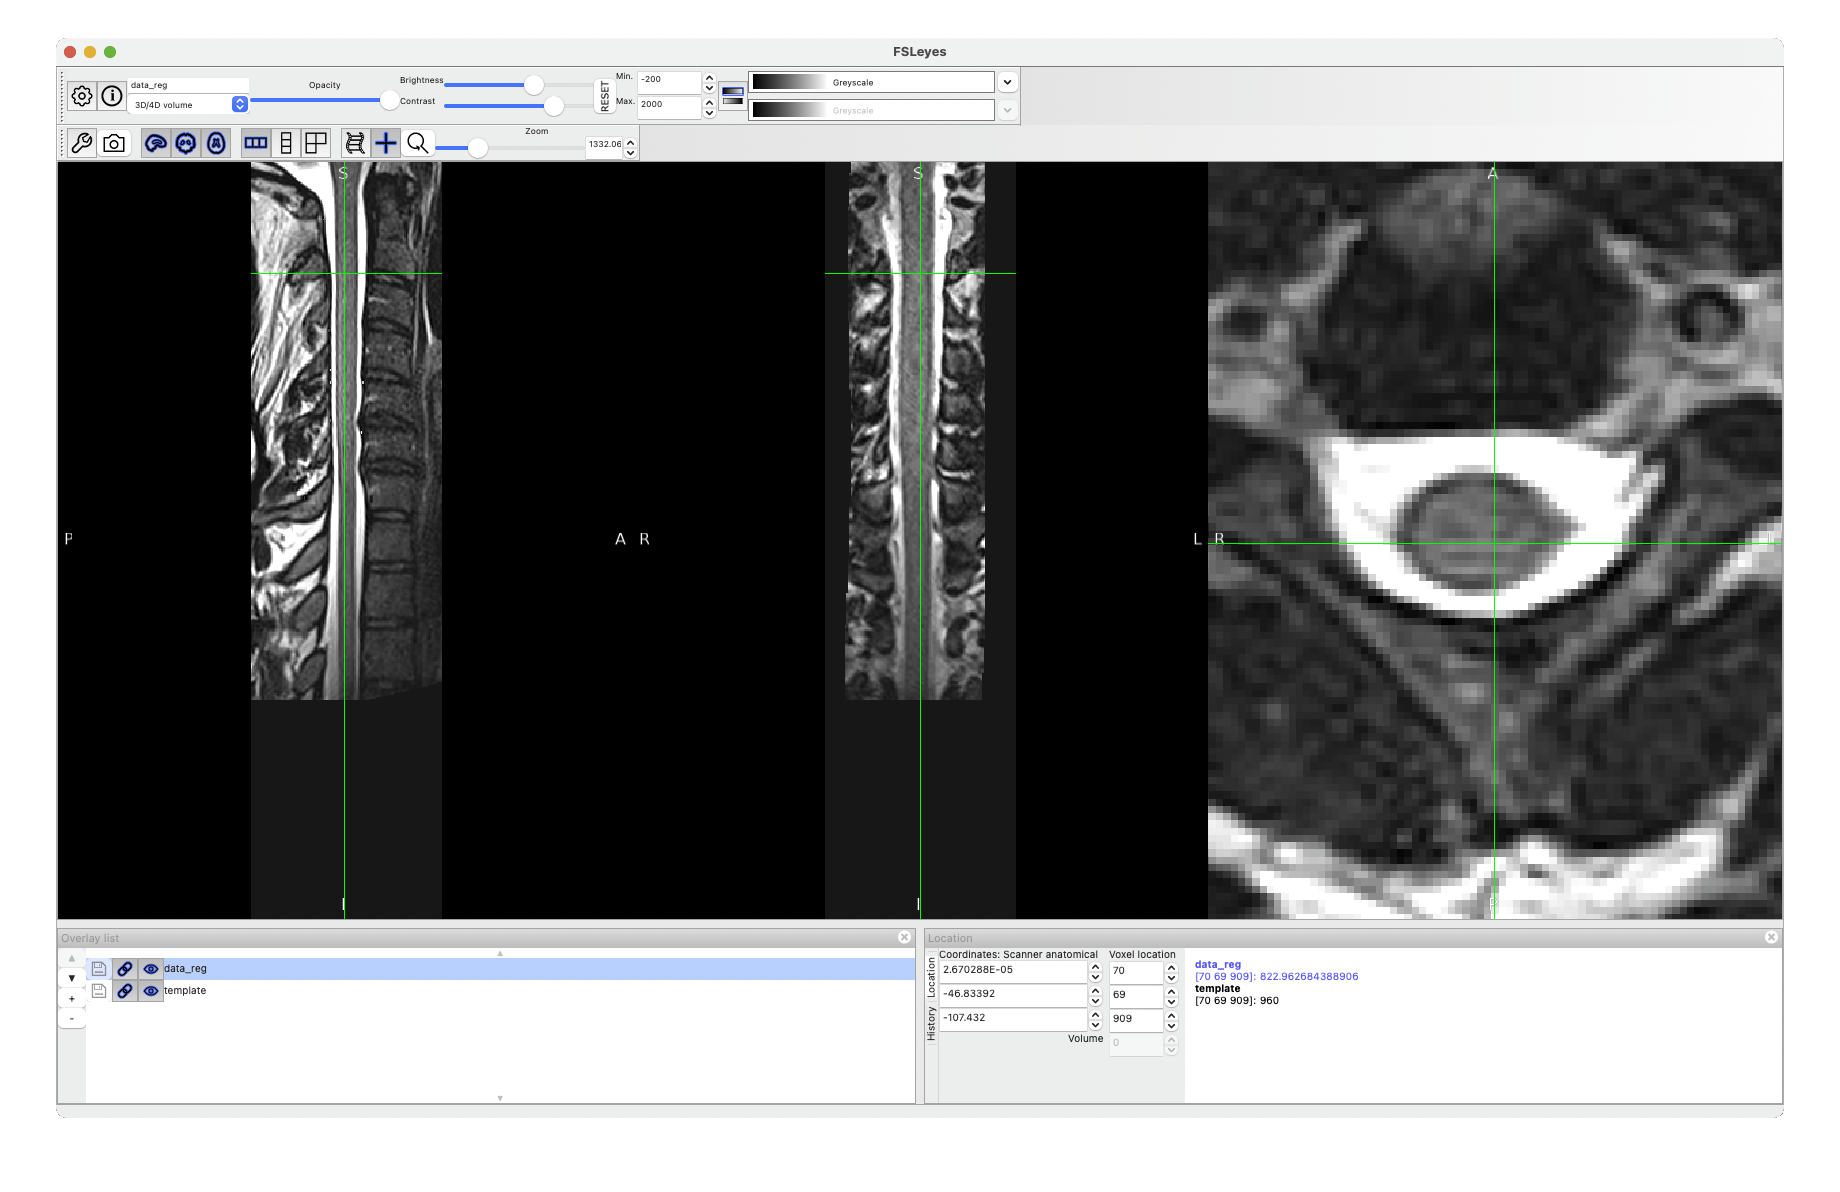

I tried running the registration using the t2_seg as the input image (since I don’t have access to it), and the registration looks OK to me:

This is what I ran:

sct_register_to_template -i t2_seg.nii.gz -s t2_seg.nii.gz -lrootlet t2_rootlets.nii.gz -ofolder ./ -c t2 -param step=1,type=seg,algo=syn,iter=0

So I suspect something is off with your T2w image. You can email it to me if you wish.